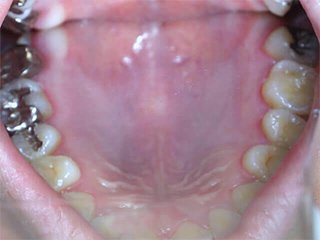

どこを治したかわかりますか?正解は、、、、、、、こうなってました。金属の詰め物、被せ物を取り、中の虫歯や金属片をきれいにし、形を整えたところです(写真は右上だけですが左上も同じようにします)。患者様が他院にて歯科治療を受け、健康保険適用の金属にて治療を終えてからもともとあったアトピー性皮膚炎が悪化し、調べたところ歯科金属アレルギーであったことが判明。当院にご相談に来られました。